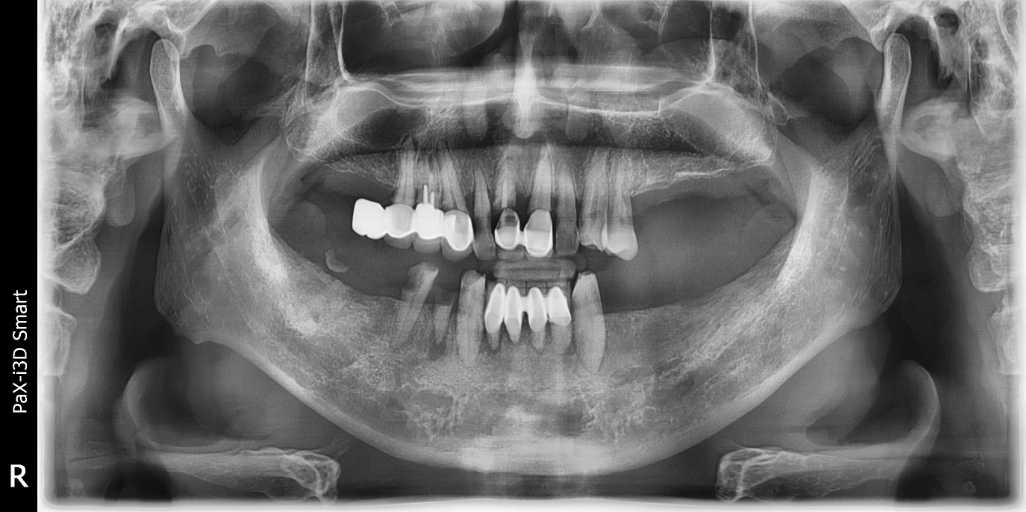

무치악 임플란트 전후 실제 사례 #3

#무치악 임플란트 환자 사례 : 기존 치아의 염증 상태로 인해 치료 시작일 때, 잔존치 전체 발치 + 상악동거상술(양쪽) + 뼈이식다수 + 임플란트 픽스처(뿌리) 17개 식립